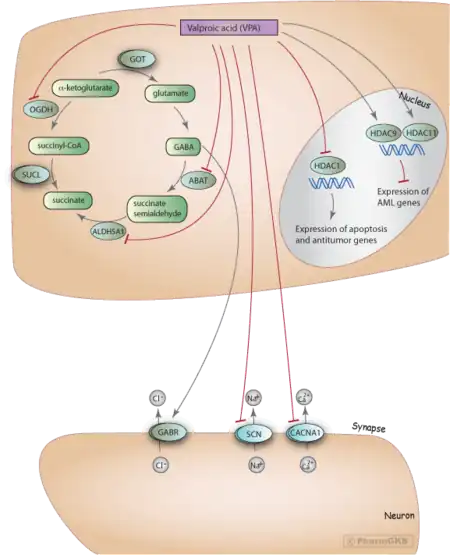

Valproate's precise mechanism of action is unclear.[1][5] Proposed mechanisms include affecting GABA levels, blocking voltage-gated sodium channels, and inhibiting histone deacetylases.[6][7] Valproic acid is a branched short-chain fatty acid (SCFA) made from valeric acid.[6]

The medication has been tested in the treatment of AIDS and cancer, owing to its histone-deacetylase-inhibiting effects.[26]

Pharmacodynamics

Although the mechanism of action of valproate is not fully understood,[54] traditionally, its anticonvulsant effect has been attributed to the blockade of voltage-gated sodium channels and increased brain levels of gamma-aminobutyric acid (GABA).[54] The GABAergic effect is also believed to contribute towards the anti-manic properties of valproate.[54] In animals, sodium valproate raises cerebral and cerebellar levels of the inhibitory synaptic neurotransmitter, GABA, possibly by inhibiting GABA degradative enzymes, such as GABA transaminase, succinate-semialdehyde dehydrogenase and by inhibiting the re-uptake of GABA by neuronal cells.[54]

Prevention of neurotransmitter-induced hyperexcitability of nerve cells, via Kv7.2 channel and AKAP5, may also contribute to its mechanism.[67] Also, it has been shown to protect against a seizure-induced reduction in phosphatidylinositol (3,4,5)-trisphosphate (PIP3) as a potential therapeutic mechanism.[68]

It also has histone-deacetylase-inhibiting effects. The inhibition of histone deacetylase, by promoting more transcriptionally active chromatin structures, likely presents the epigenetic mechanism for regulation of many of the neuroprotective effects attributed to valproic acid. Intermediate molecules mediating these effects include VEGF, BDNF, and GDNF.[69][70]